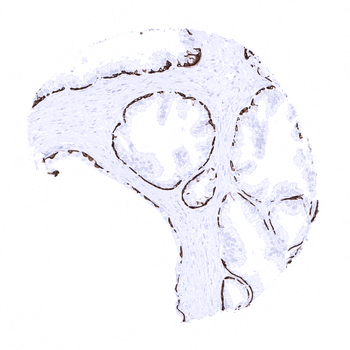

Strong KRT14 positivity in basal cells of the prostate.